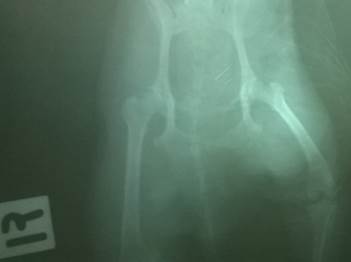

进行推拿后几小时,该犬就可以行走;2天后可以正常行走;1个月后完全恢复,正常活动。X线片显示髋关节已完全复位(见图2)。

图2:治疗前后髋关节X线照片